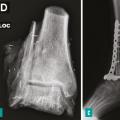

Prise en charge chirurgicale des sarcomes osseux

La résection d’un sarcome osseux a pour objectif d’obtenir des marges adaptées, en privilégiant les chirurgies conservatrices, tout en s’efforçant de préserver la meilleure qualité de vie.1 La chirurgie doit être effectuée par une équipe spécialisée dans un centre de référence intégré au réseau NetSarc+, ce qui diminue le risque de…